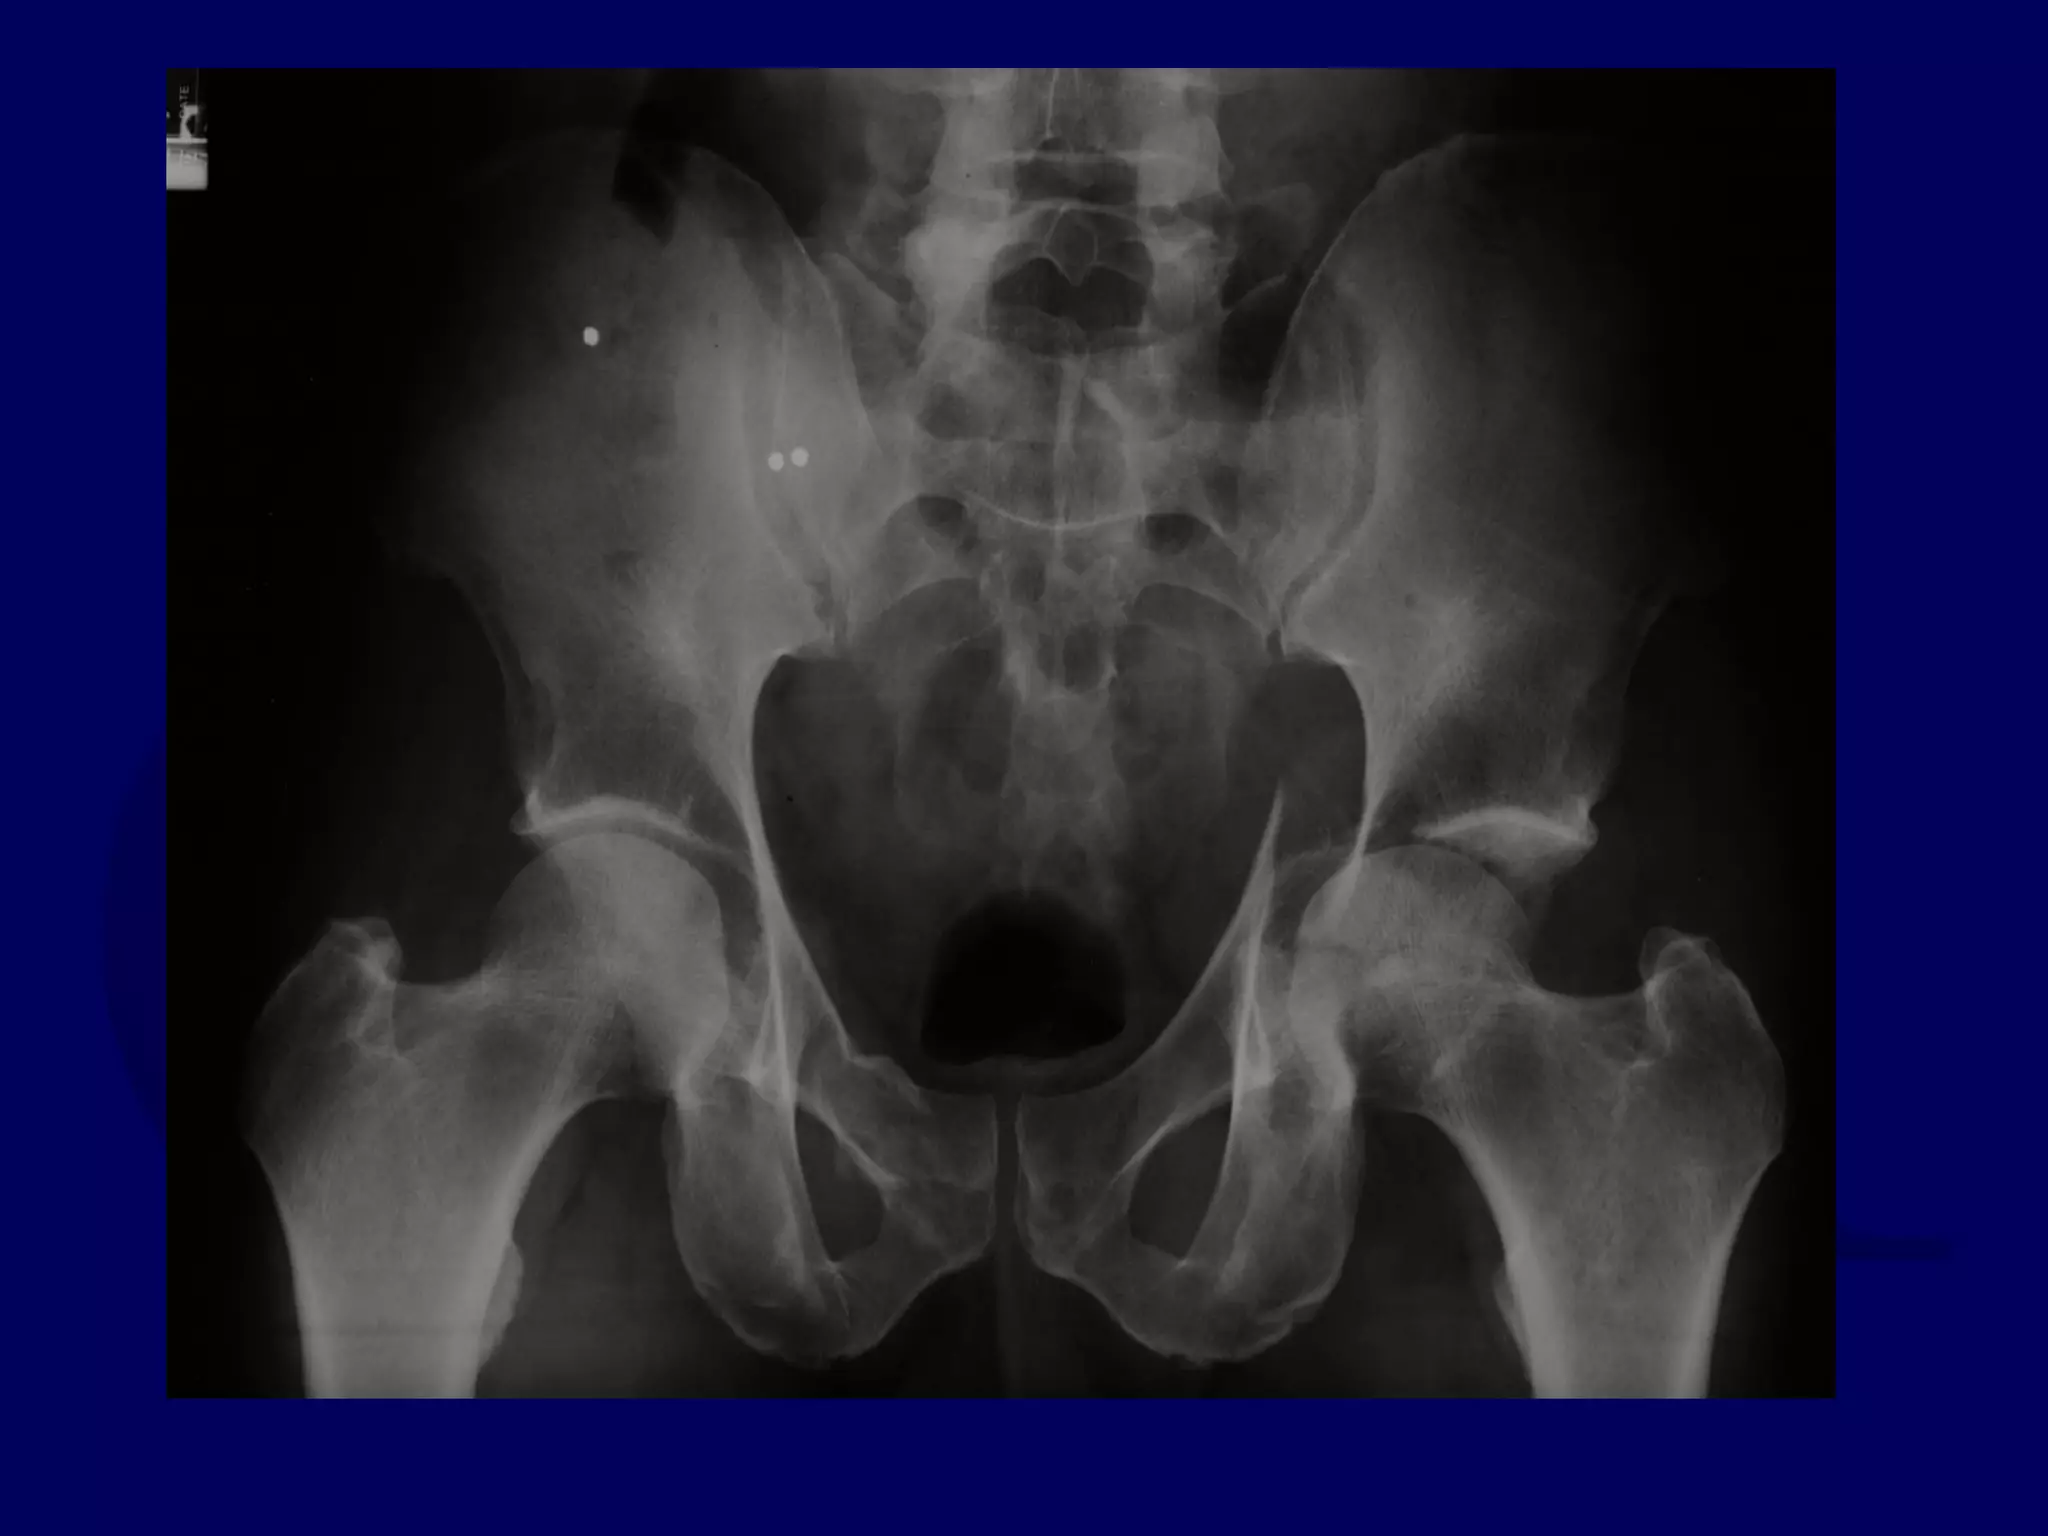

Special Case

“T-Type” Acetabular Fracture

Proximal Femur Fracture

14 y.o. Male

Sequential K-L / Ilioinguinal

Approaches